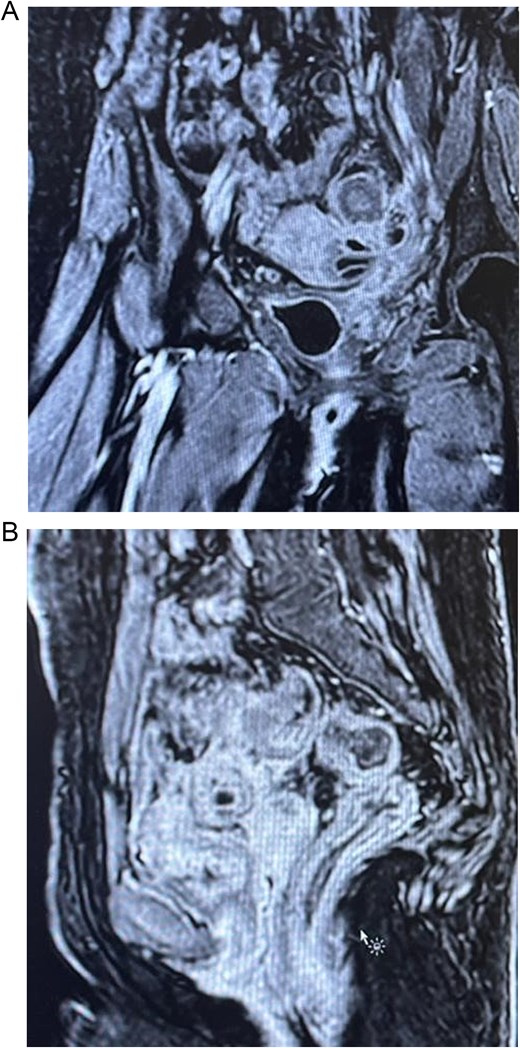

Colonoscopy showed severe luminal narrowing between the junction of the sigmoid and descending colon. Diagnostic cystoscopy confirmed the presence of a fistula opening and demonstrated a villous-like reaction in the urinary bladder mucosa, consistent with a fistulous connection. The fistula opening was located low, raising the possibility of vesicovaginal fistula. Magnetic resonance imaging (MRI) of the abdomen conformed sigmoid diverticulitis and fistula tract to urinary bladder and also possibly a fistula tract extending to the mid-rectum (Fig. 2).